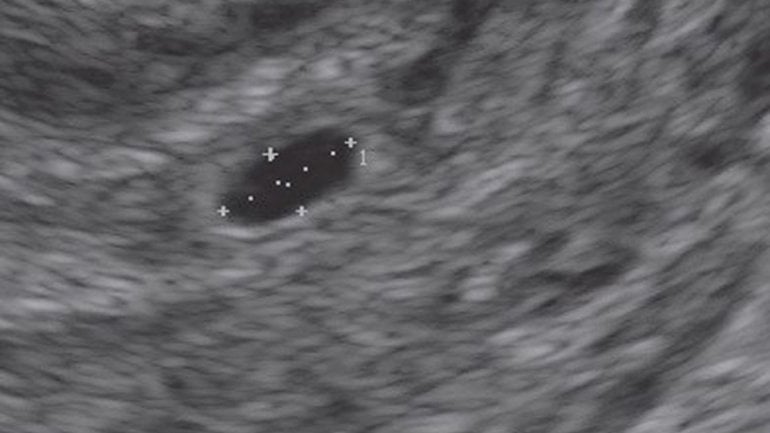

Ultraschall 5. SSW

Rechts im Bild ist die Fruchthöhle (schwarz) zu sehen. Der Embryo ist jetzt etwa zwei Millimeter lang und auf dem Ultraschall zu dieser Zeit oft noch nicht zu erkennen. Trotzdem beginnt in dieser Woche das Herz des Embryos zu schlagen.